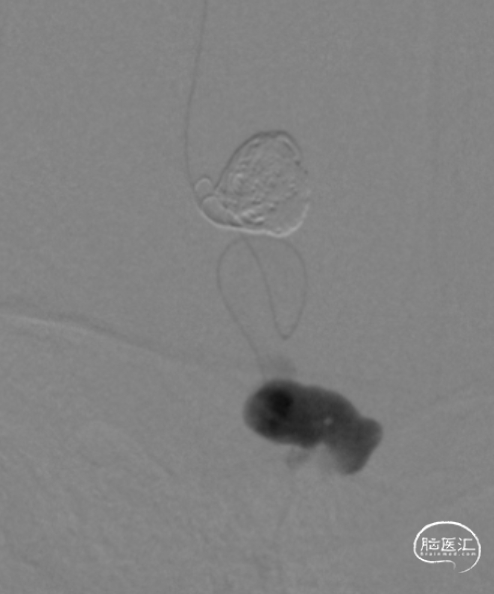

DCwire™微导丝配合Echelon微导管、通过优秀的扭控到位性及输送性,为微导管顺利到位提供保障。通过Echelon微导管首先稳定栓塞近端静脉球。

近端静脉球弹簧圈致密栓塞后,经马拉松微导管注入Onyx18。

顺利“安全”地注入Onyx18,瘘口完全栓塞,造影提示一期治愈,正常皮层引流静脉得以保留。